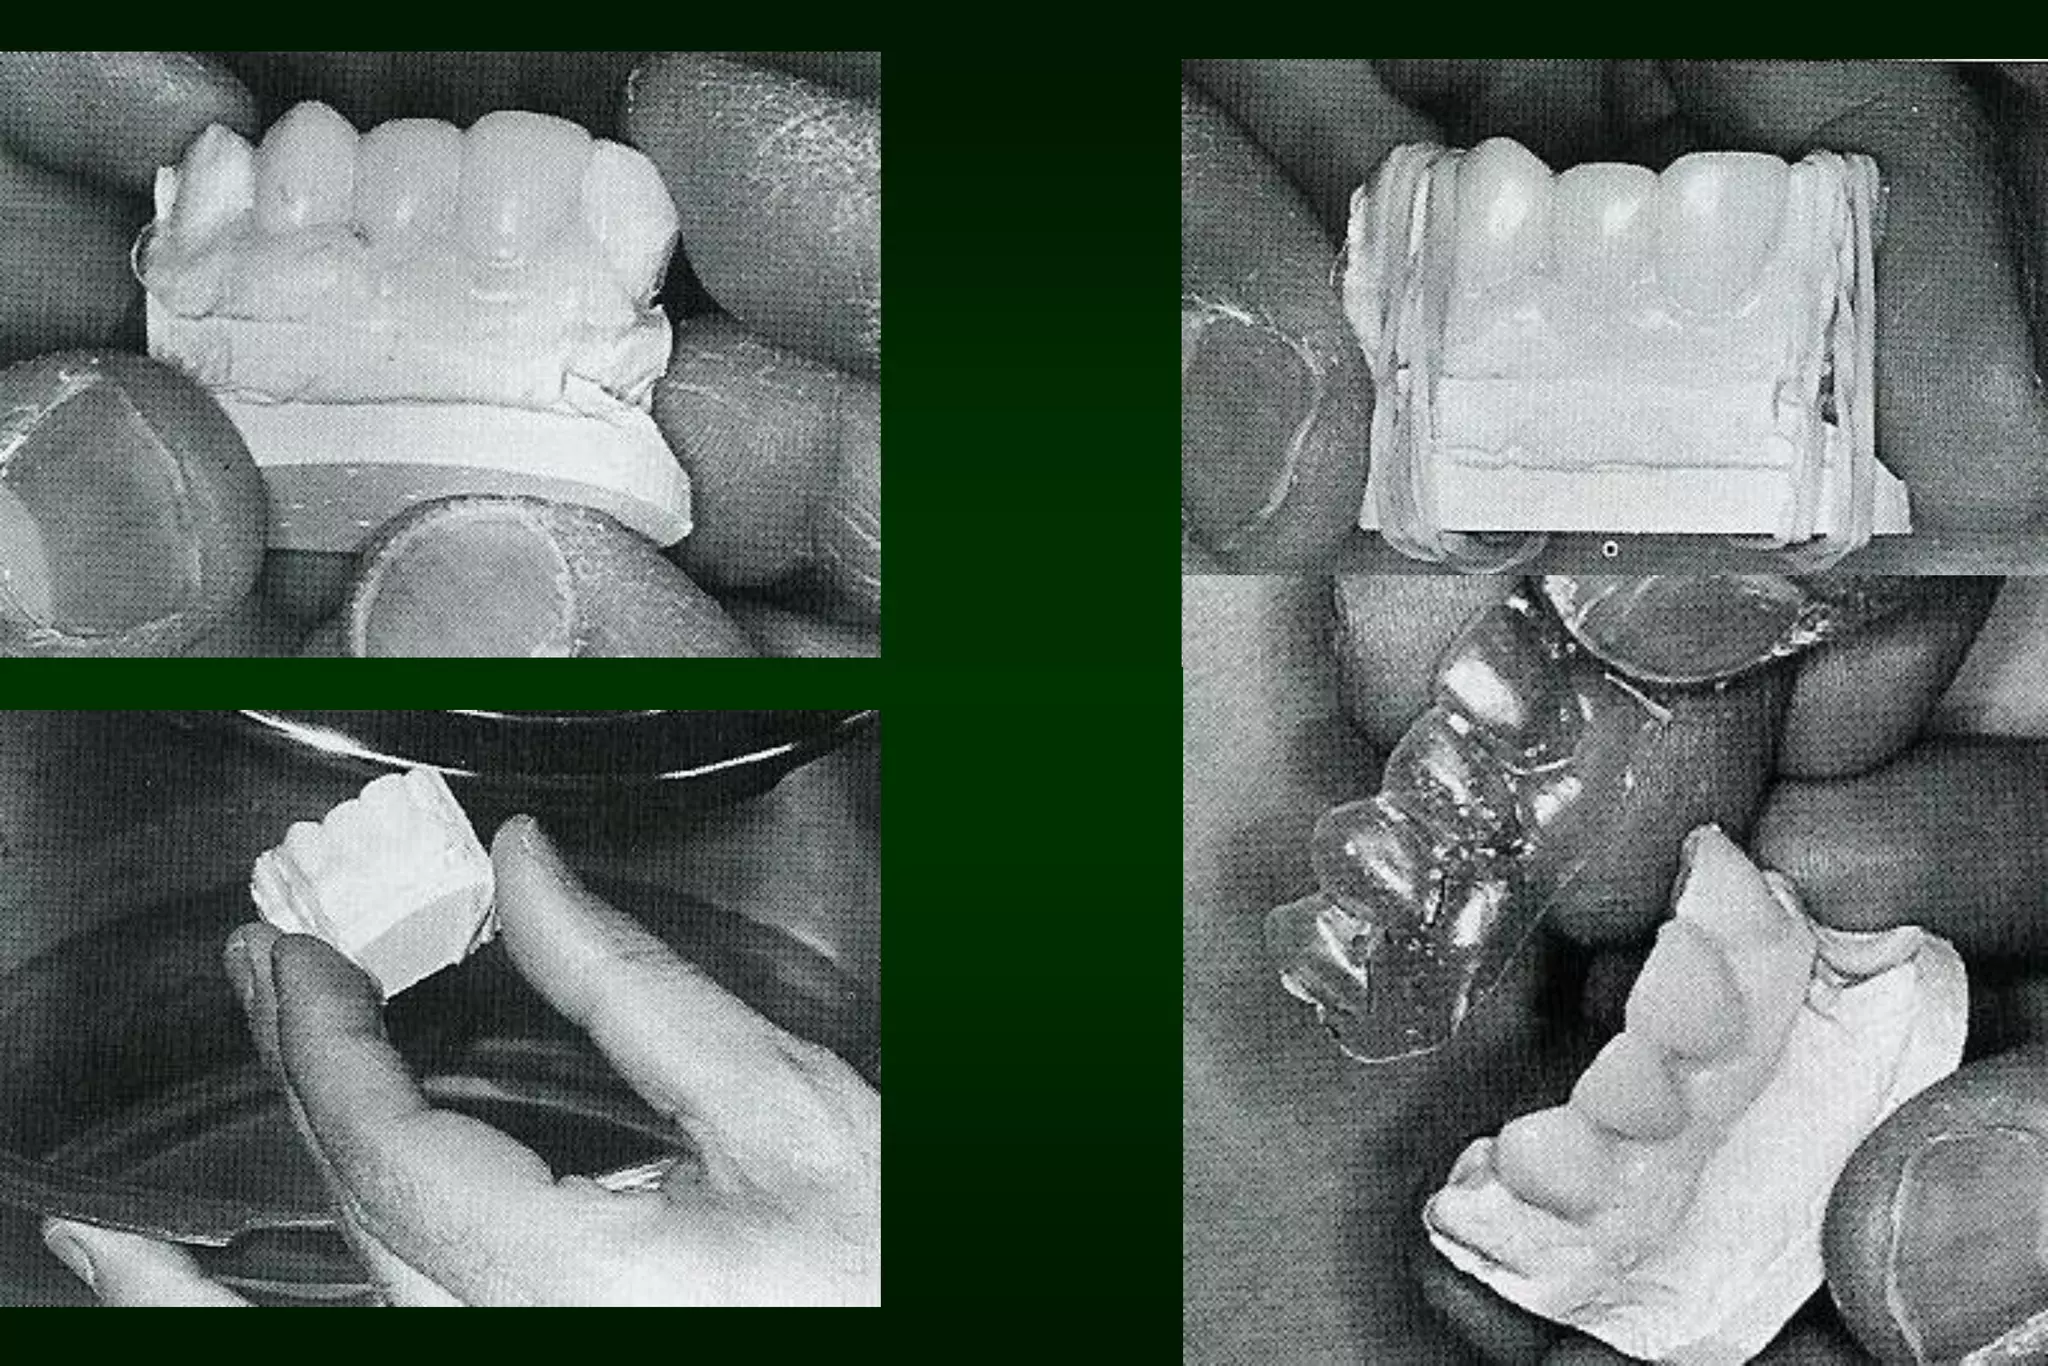

Types of Provisional Restoration II.Customized resin restorations 1. Direct technique a. Direct matrix-assisted • • Elastomeric or alginate impression Vacuum formed plastic template

Types of Provisional Restoration II.Customized resin restorations 2. Indirect technique • • Initial and final polymerizations occur extraorally The first step is preparing a index (e.g. vacuum shell) on study cast prior to tooth preparation visit